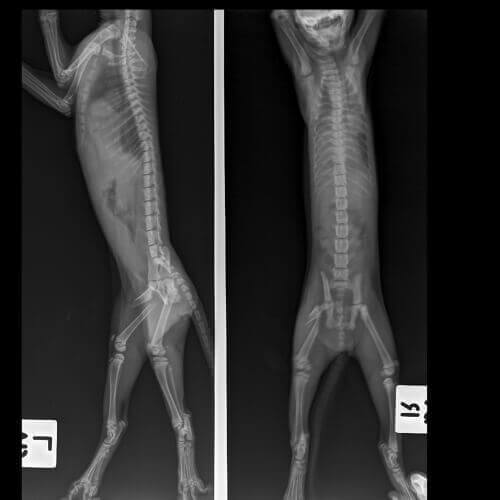

- Røntgenbilleder